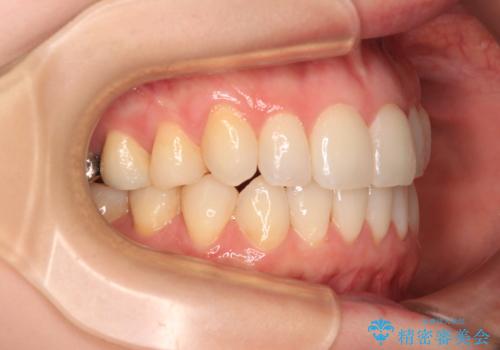

- 前歯のデコボコや八重歯の様になっていることを気にして来院された患者様です。

犬歯捻れて前方に飛び出しており、下顎前歯もそれに沿うようにデコボコとなっていました。

IPR(歯と歯の間を削る処置)によりスペースを獲得して上下顎前歯のデコボコを改善し、前歯が前方に突出しないように設定した上で、インビザラインにて矯正治療を行うこととしました。